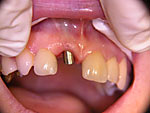

Frontzahn-Implantation: